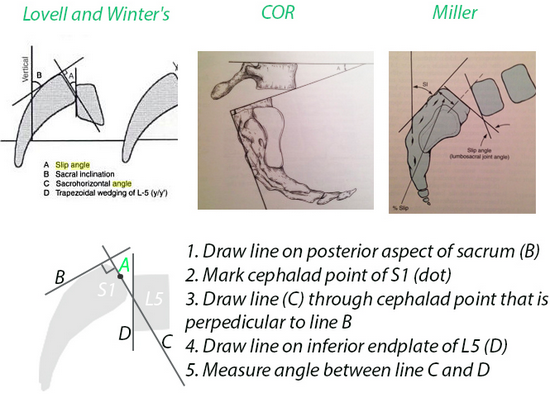

Slip angle greater than what degree is associated with greater risk of progression?

>50 degrees